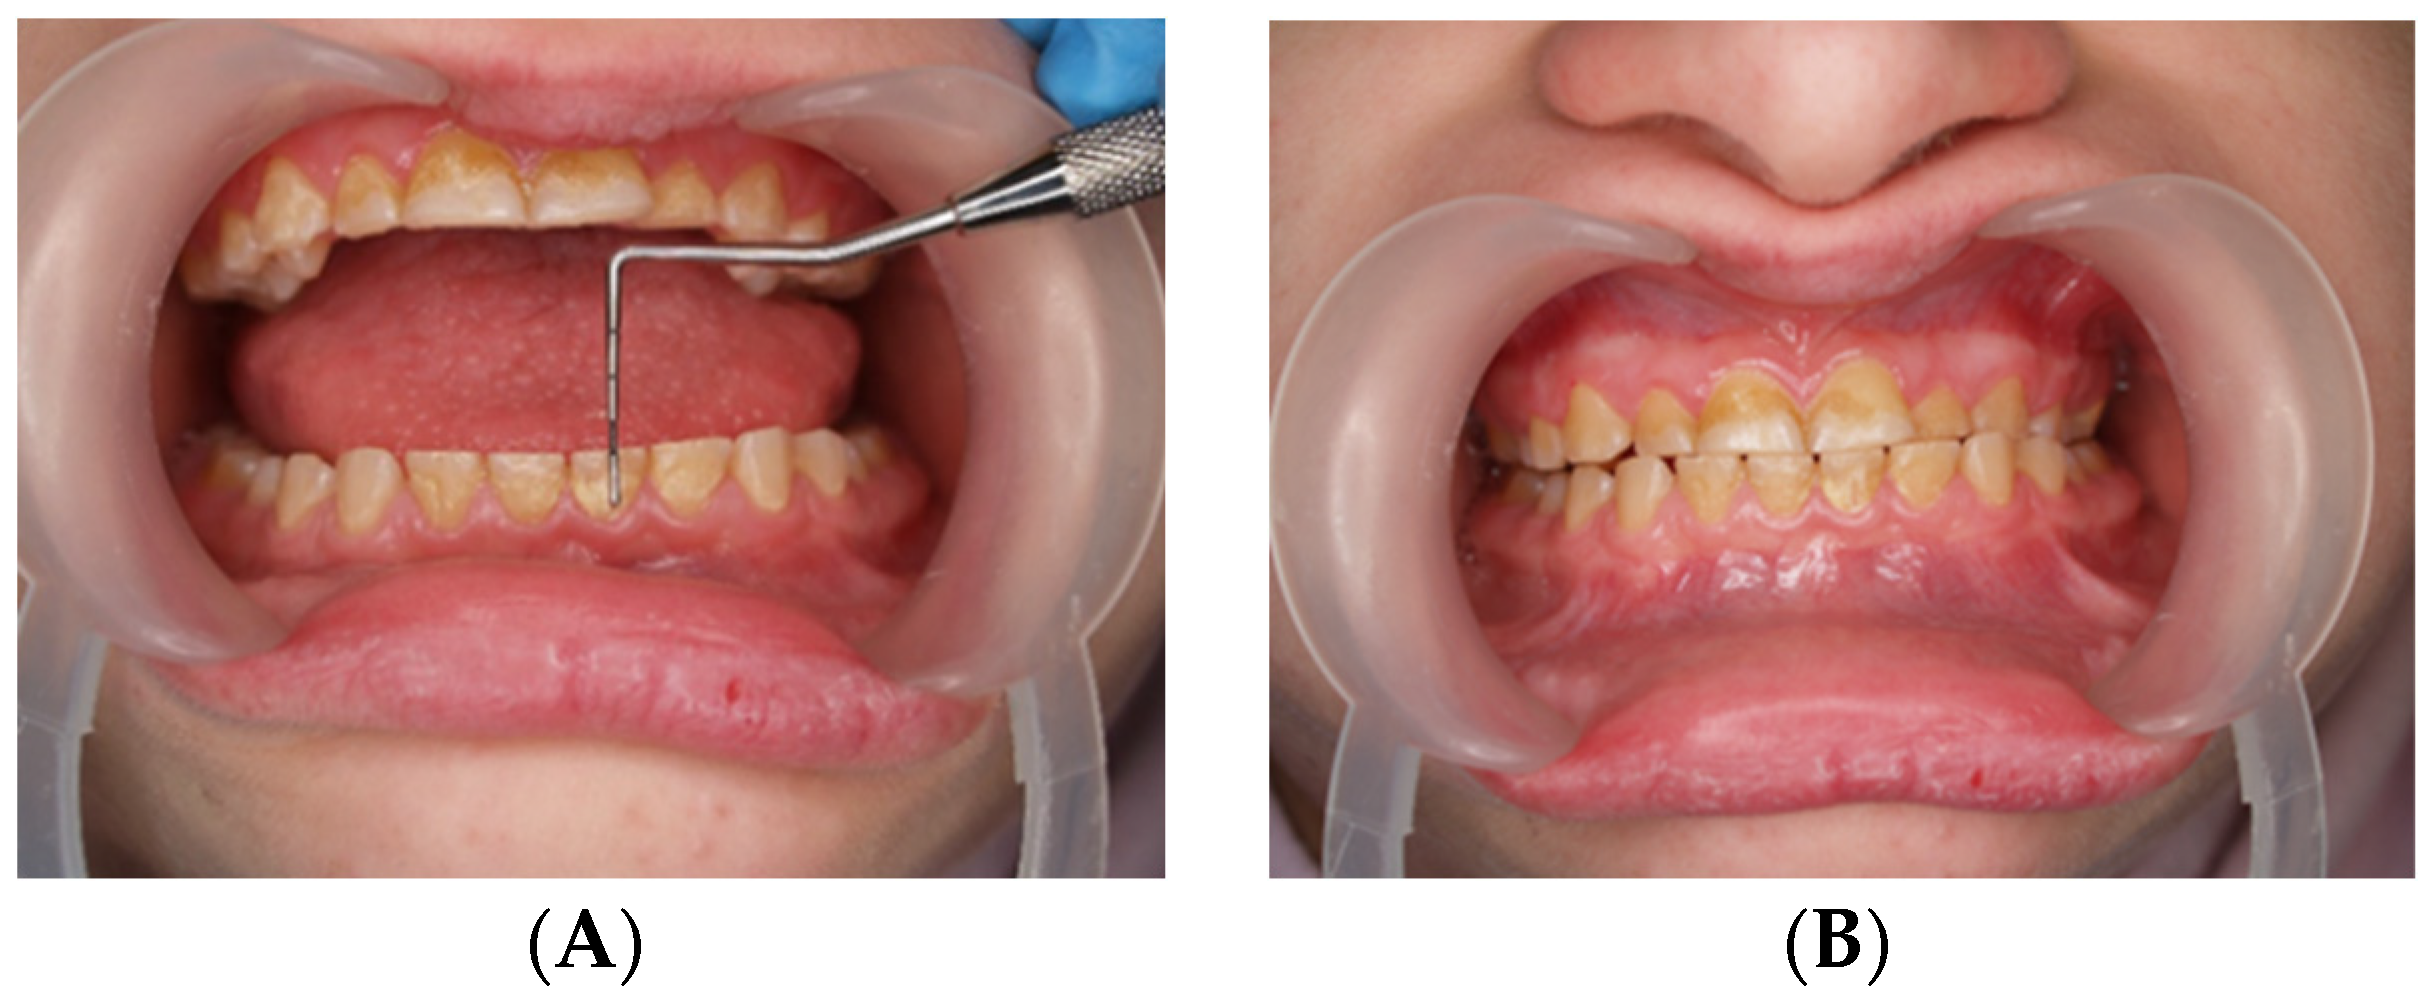

Figure 3.

(A,B) Assessment of the height of worn teeth.

During the first adaptation visit, the patient underwent a clinical palpation examination to assess the height of the mandibular occlusion and severity of tooth wear, the range of jaw abduction, and hypermobility in the temporomandibular joint. There was no limitation of jaw mobility (positive three-finger test). The resting position of the lower jaw is shown in Figure 1. However, a left-sided lateral crossbite was found (Figure 2) and pathological tooth wear in the range of 1/4–1/3 of the height of the clinical crown was found (Figure 3). The intraoral examination assessed the angle class, cuspid class, vertical and horizontal overbite, and incisor protrusion/retrusion. Tongue dysfunction and tension of facial and masticatory muscles were also assessed. The patient was diagnosed with a skeletal class III malocclusion and had an oral hygiene index OHI 6, bleeding on probing BoP 40%, and approximal plaque index API 50%.